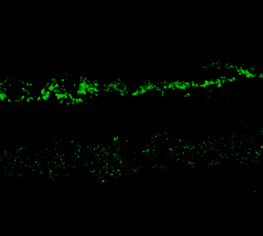

Immunostaining of rabbit retina showing NR2A in the rod and cone photoreceptors in the outer plexiform layer as well as the entire inner plexiform layer. |